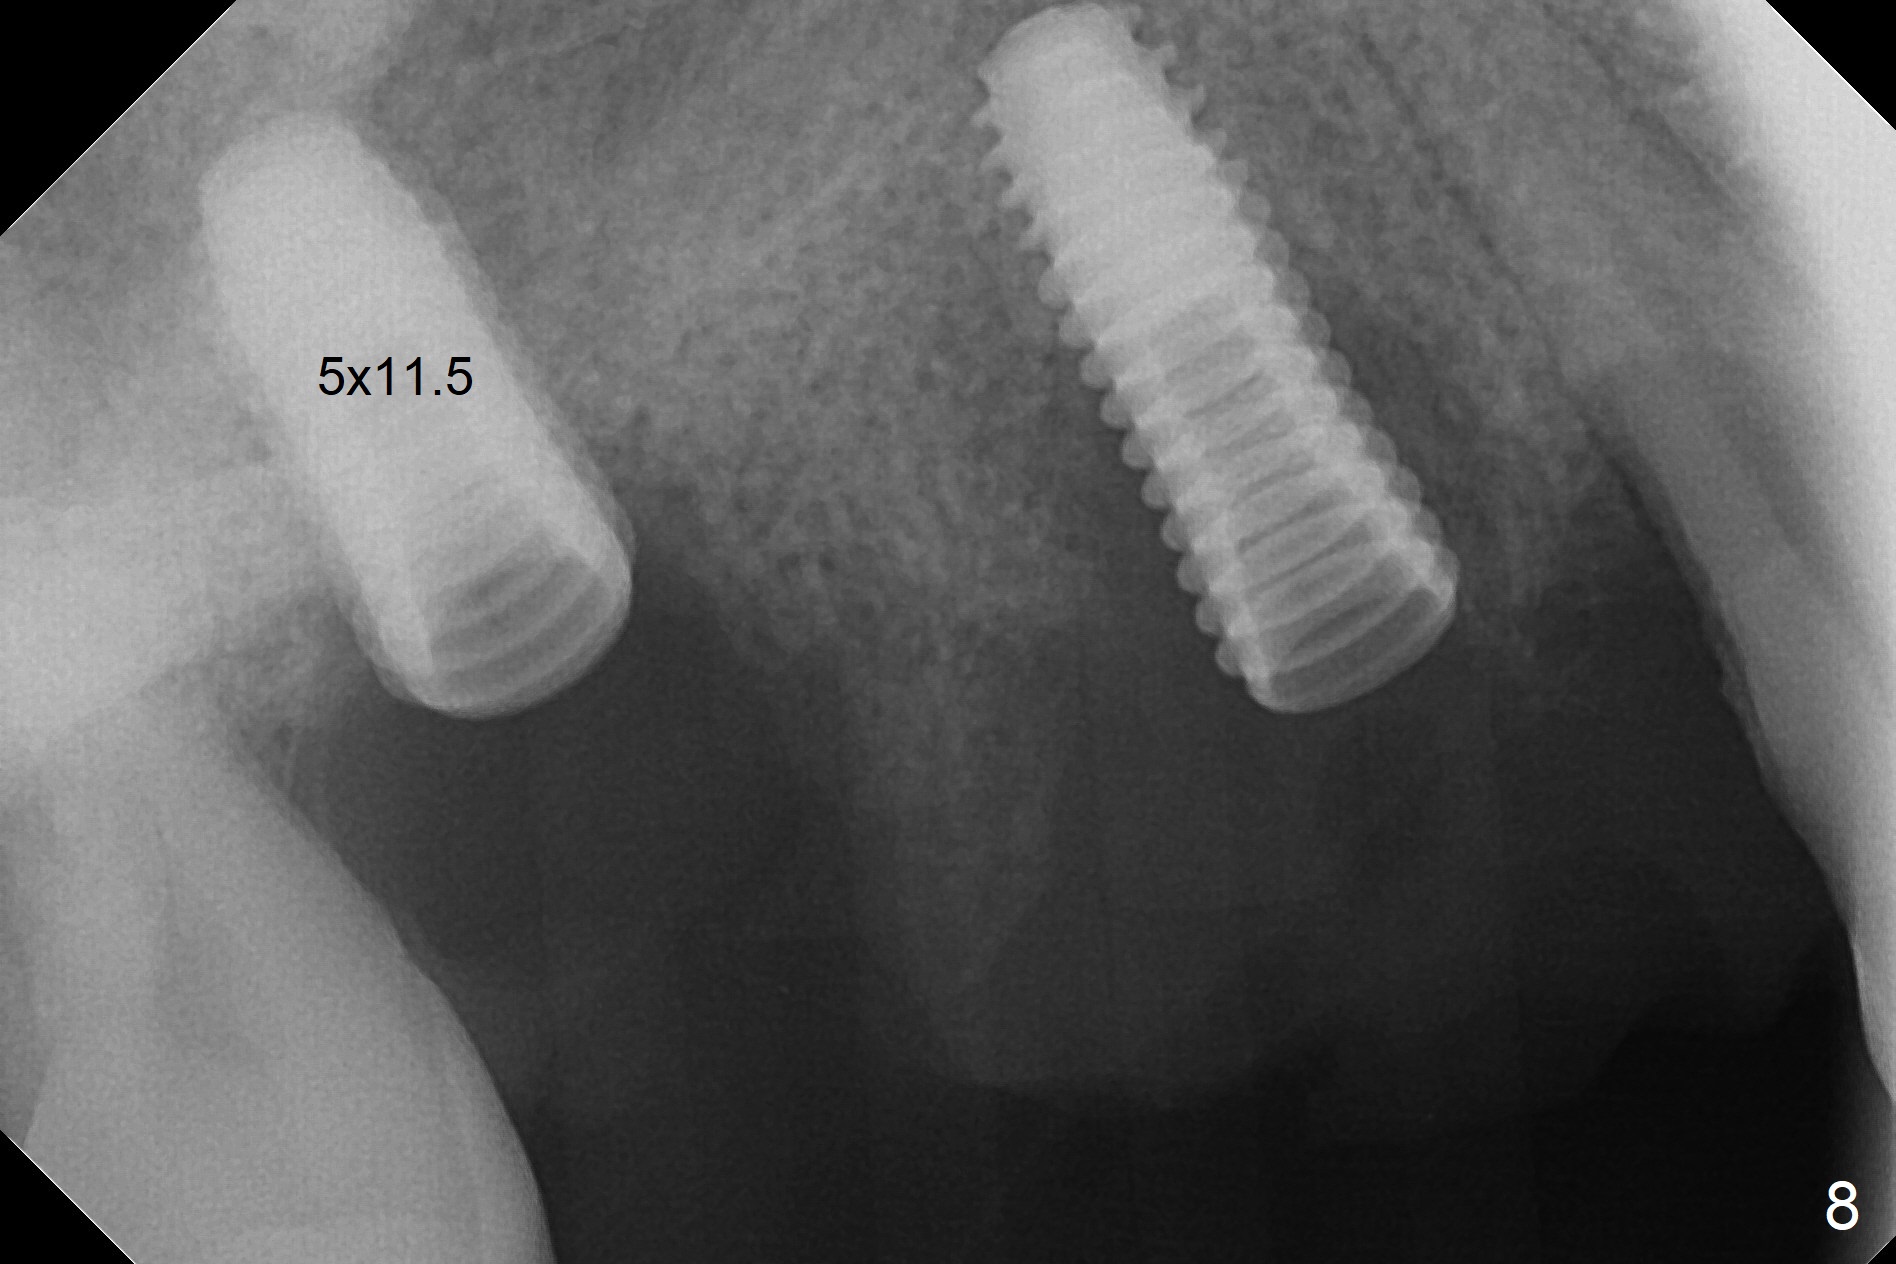

The 36-year-old man (ex-smoker, quit for 4-5 years) insists upon #3 and 5 extraction first for implants, in spite of more severe infection at #7, 14,19,30 (Fig.1-4). The gingiva around #23-26 implants is healthy 3 weeks postop (Fig.5). The initial depths at #3 and 5 are 8.5 mm (bone-level) and 18 mmm (gingiva-level (13 mm (implant length) + 5 mm cuff), respectively. When a drill penetrates the sinus floor, confirm the depth. After use of 3.8 mm drill, 4.5 mm tap drill is inserted at #3 without stability, while a 4.5x13 mm implant is placed at #5 with primary stability (Fig.6,7). Then a 5x11.5 mm is placed at #3 subcrestal proximally after sinus lift with Vanilla graft (without sinus membrane perforation; Fig.8). The implant at #5 is seated ~1 mm deeper (subcrestal mesially (^^); supracrestal distally (^)); allograft is placed around the implants prior to insertion of 6.5x7(5) and 5.5x4(5) mm abutments; last more allograft is added (Fig.9 *, 10). The implants seem to have been osteointegrated 4.5 months postop (Fig.11,12). The gingiva is healthy around the implants without bone loss 3 months post cementation (Fig.13,14).